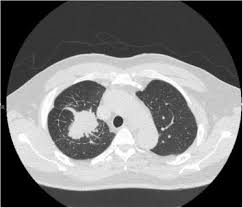

Can Lung Cancer Be Mistaken For Tuberculosis / Cancer And Tb / Since mycobacterium tuberculosis (mtb) is an intracellular organism, bacterial dna could integrate to bronchial epithelial cells inducing neoplastic transformation.. Primary tuberculosis usually begins in childhood and affects the lungs and bronchial lymphatic glands of the lung roots. Tuberculosis (tb) is a contagious infection that usually attacks your lungs. The occurrence of pulmonary tuberculosis (ptb) and lung cancer as comorbidities has been extensively discussed in many studies. Most lung cancers do not cause any symptoms until they have spread, but some people with early lung cancer do have symptoms. Pulmonary tuberculosis is caused by mycobacterium tuberculosis, which produces characteristic tuberculosis changes in the lung.

Difference between lung cancer and tuberculosis. This growth can spread beyond the lung by the process of metastasis into nearby tissue or other parts of the body. Selection of the most suitable tests for detection of m. However, this can also occur with tuberculosis or a pulmonary embolism. Concomitant active tuberculosis in nsclc (tblc) resembles locoregional immunotherapy of tumor cell vaccine; Primary tuberculosis clinical forms the primary site of infection in the lungs is called the ghon focus. Living with advanced breast cancer. Symptoms of tuberculosis and lung cancer are overlapping and it is difficult to differentiate without the histopathological report. When people with lung tb cough, sneeze or spit, they propel the tb germs into the air. Lung cancer and pulmonary tuberculosis (tb) comorbidity is a clinical problem that presents a challenge for the diagnosis and treatment of both diseases.objective: Tuberculosis (tb) is a potentially serious infectious disease that mainly affects the lungs. Primary tuberculosis usually begins in childhood and affects the lungs and bronchial lymphatic glands of the lung roots. You can't get it from shaking hands with someone who has it or by sharing their food or drink.

Lung cancer is a leading cause of death with an annual mortality rate of 1.59 million people, accounting for 19.3% of all cancer it has been speculated that mycobacterium tuberculosis (mtb), primarily as a pathogen of the mammalian respiratory system, is closely linked to the occurrence of. Lung cancer and pulmonary tuberculosis (tb) comorbidity is a clinical problem that presents a challenge for the diagnosis and treatment of both diseases.objective: Lung cancer is often divided into two types: You can get tb by breathing in air droplets from a cough or sneeze of an infected person. Pulmonary tb is caused by the bacterium mycobacterium tuberculosis (m tuberculosis). Concomitant active tuberculosis in nsclc (tblc) resembles locoregional immunotherapy of tumor cell vaccine; 90% of cases being attributable to smoking. However, this can also occur with tuberculosis or a pulmonary embolism. Tuberculosis infection should be based on the reasons and the context for testing, test availability, and overall cost. This growth can spread beyond the lung by the process of metastasis into nearby tissue or other parts of the body. Patients with lung cancer are often misdiagnosed as pulmonary tuberculosis leading to delay in the correct diagnosis as well as exposure to inappropriate. Tuberculosis germs don't thrive on surfaces. Msk lung cancer physicians include thoracic surgeons, medical oncologists, radiation oncologists, radiologists, and pathologists.

Selection of the most suitable tests for detection of m. Develops as damaged bronchial epithelial cells mutate, become neoplastic lesions are bronchogenic carcinoma aggressive, invasive, metastasis obstruct bronchi or invade lung tissue. In the past, it was well known that lung cancer is a specific epidemiological successor of ptb and that lung cancer often develops in scars caused by ptb. Pleural effusion may develop in lung cancer, breast cancer, lymphoma, lymphogranulematosis, benign and malignant pleural mesothelioma, bacterial 3.2. It is most commonly caused by aspiration of oral secretions by patients who have impaired consciousness. Tb and lung cancer have been confused and misdiagnosed for centuries 2. There is especially in countries with low tb incidence diagnostic challenges with risk of diagnosis getting missed. The occurrence of pulmonary tuberculosis (ptb) and lung cancer as comorbidities has been extensively discussed in many studies. Why has this disease, once thought to be confined to the. This means the bacteria are easily spread from an infected person to someone else. This is one reason that it is among the most deadly of cancer groups. Symptoms of tuberculosis and lung cancer are overlapping and it is difficult to differentiate without the histopathological report. Methods retrospective review of nsclc.